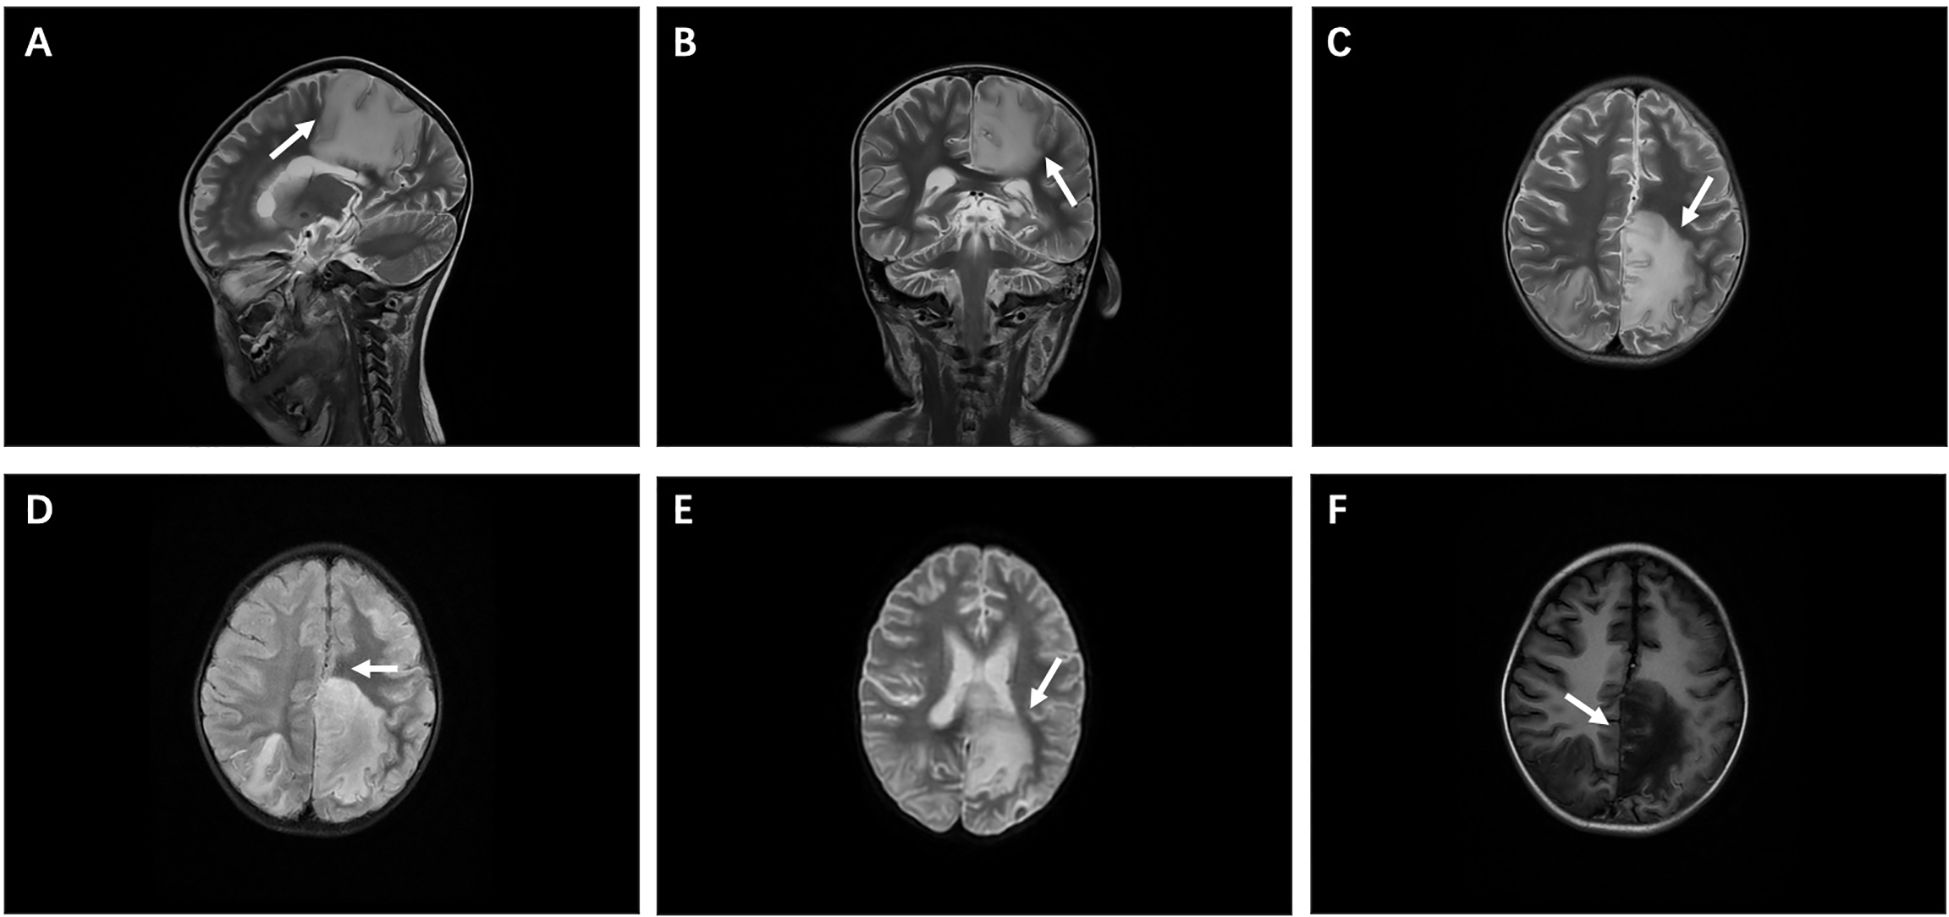

Following admission, the patient developed central respiratory failure and acute intracranial hypertension syndrome, strongly indicating CNS involvement. Therefore, a series of examinations were conducted on the central nervous system. The patient subsequently showed increased muscle tone in the right limb and positive Babinski sign on both sides. Cerebrospinal fluid (CSF) cytology indicated a positive protein qualitative test. The number of cerebrospinal fluid cells is 28 × 106/L, mainly lymphocytes, with a protein concentration of 5,110 mg/L (80–430 mg/L), a glucose concentration of 3.72 mmol/L (2.5-4.5 mmol/L), and chloride level of 116.2 mmol/L (120–130 mmol/L). No clear malignant cells were found. Basic CSF tests suggested severe impairment of the blood–brain barrier, with an increased CSF IgG synthesis index and an elevated 24-h intrathecal IgG synthesis rate. Other test results are mainly within the normal range, including cerebrospinal fluid smear, cerebrospinal fluid cryptococcal antigen, and cerebrospinal fluid culture. Cranial magnetic resonance imaging (MRI) indicated abnormal signal intensities in multiple brain regions, a nodular lesion suspicious for lymphoma in the left cerebellar hemisphere, linear leptomeningeal enhancement with associated small nodules on the left, and enhancing nodules in the right temporal lobe (Figure 1). Based on these findings, neuroradiology assessment raised a suspicion for intracranial lymphoma. However, definitive histopathological confirmation via biopsy was declined by the family.

Figure 1

Imaging manifestations. (A, B) Sagittal and coronal views of cranial magnetic resonance imaging (MRI). (C-E) T2-weighted imaging (T2WI), fluid-attenuated inversion recovery (Flair), and diffusion-weighted imaging (DWI) show high signal intensity, mainly in the left frontal cortex and subcortical area, with the left parietal lobe reaching the deep white matter area, adjacent to the affected corpus callosum, and the midline of compression shifted to the right. (F) T1-weighted imaging (T1WI) shows low signal intensity.